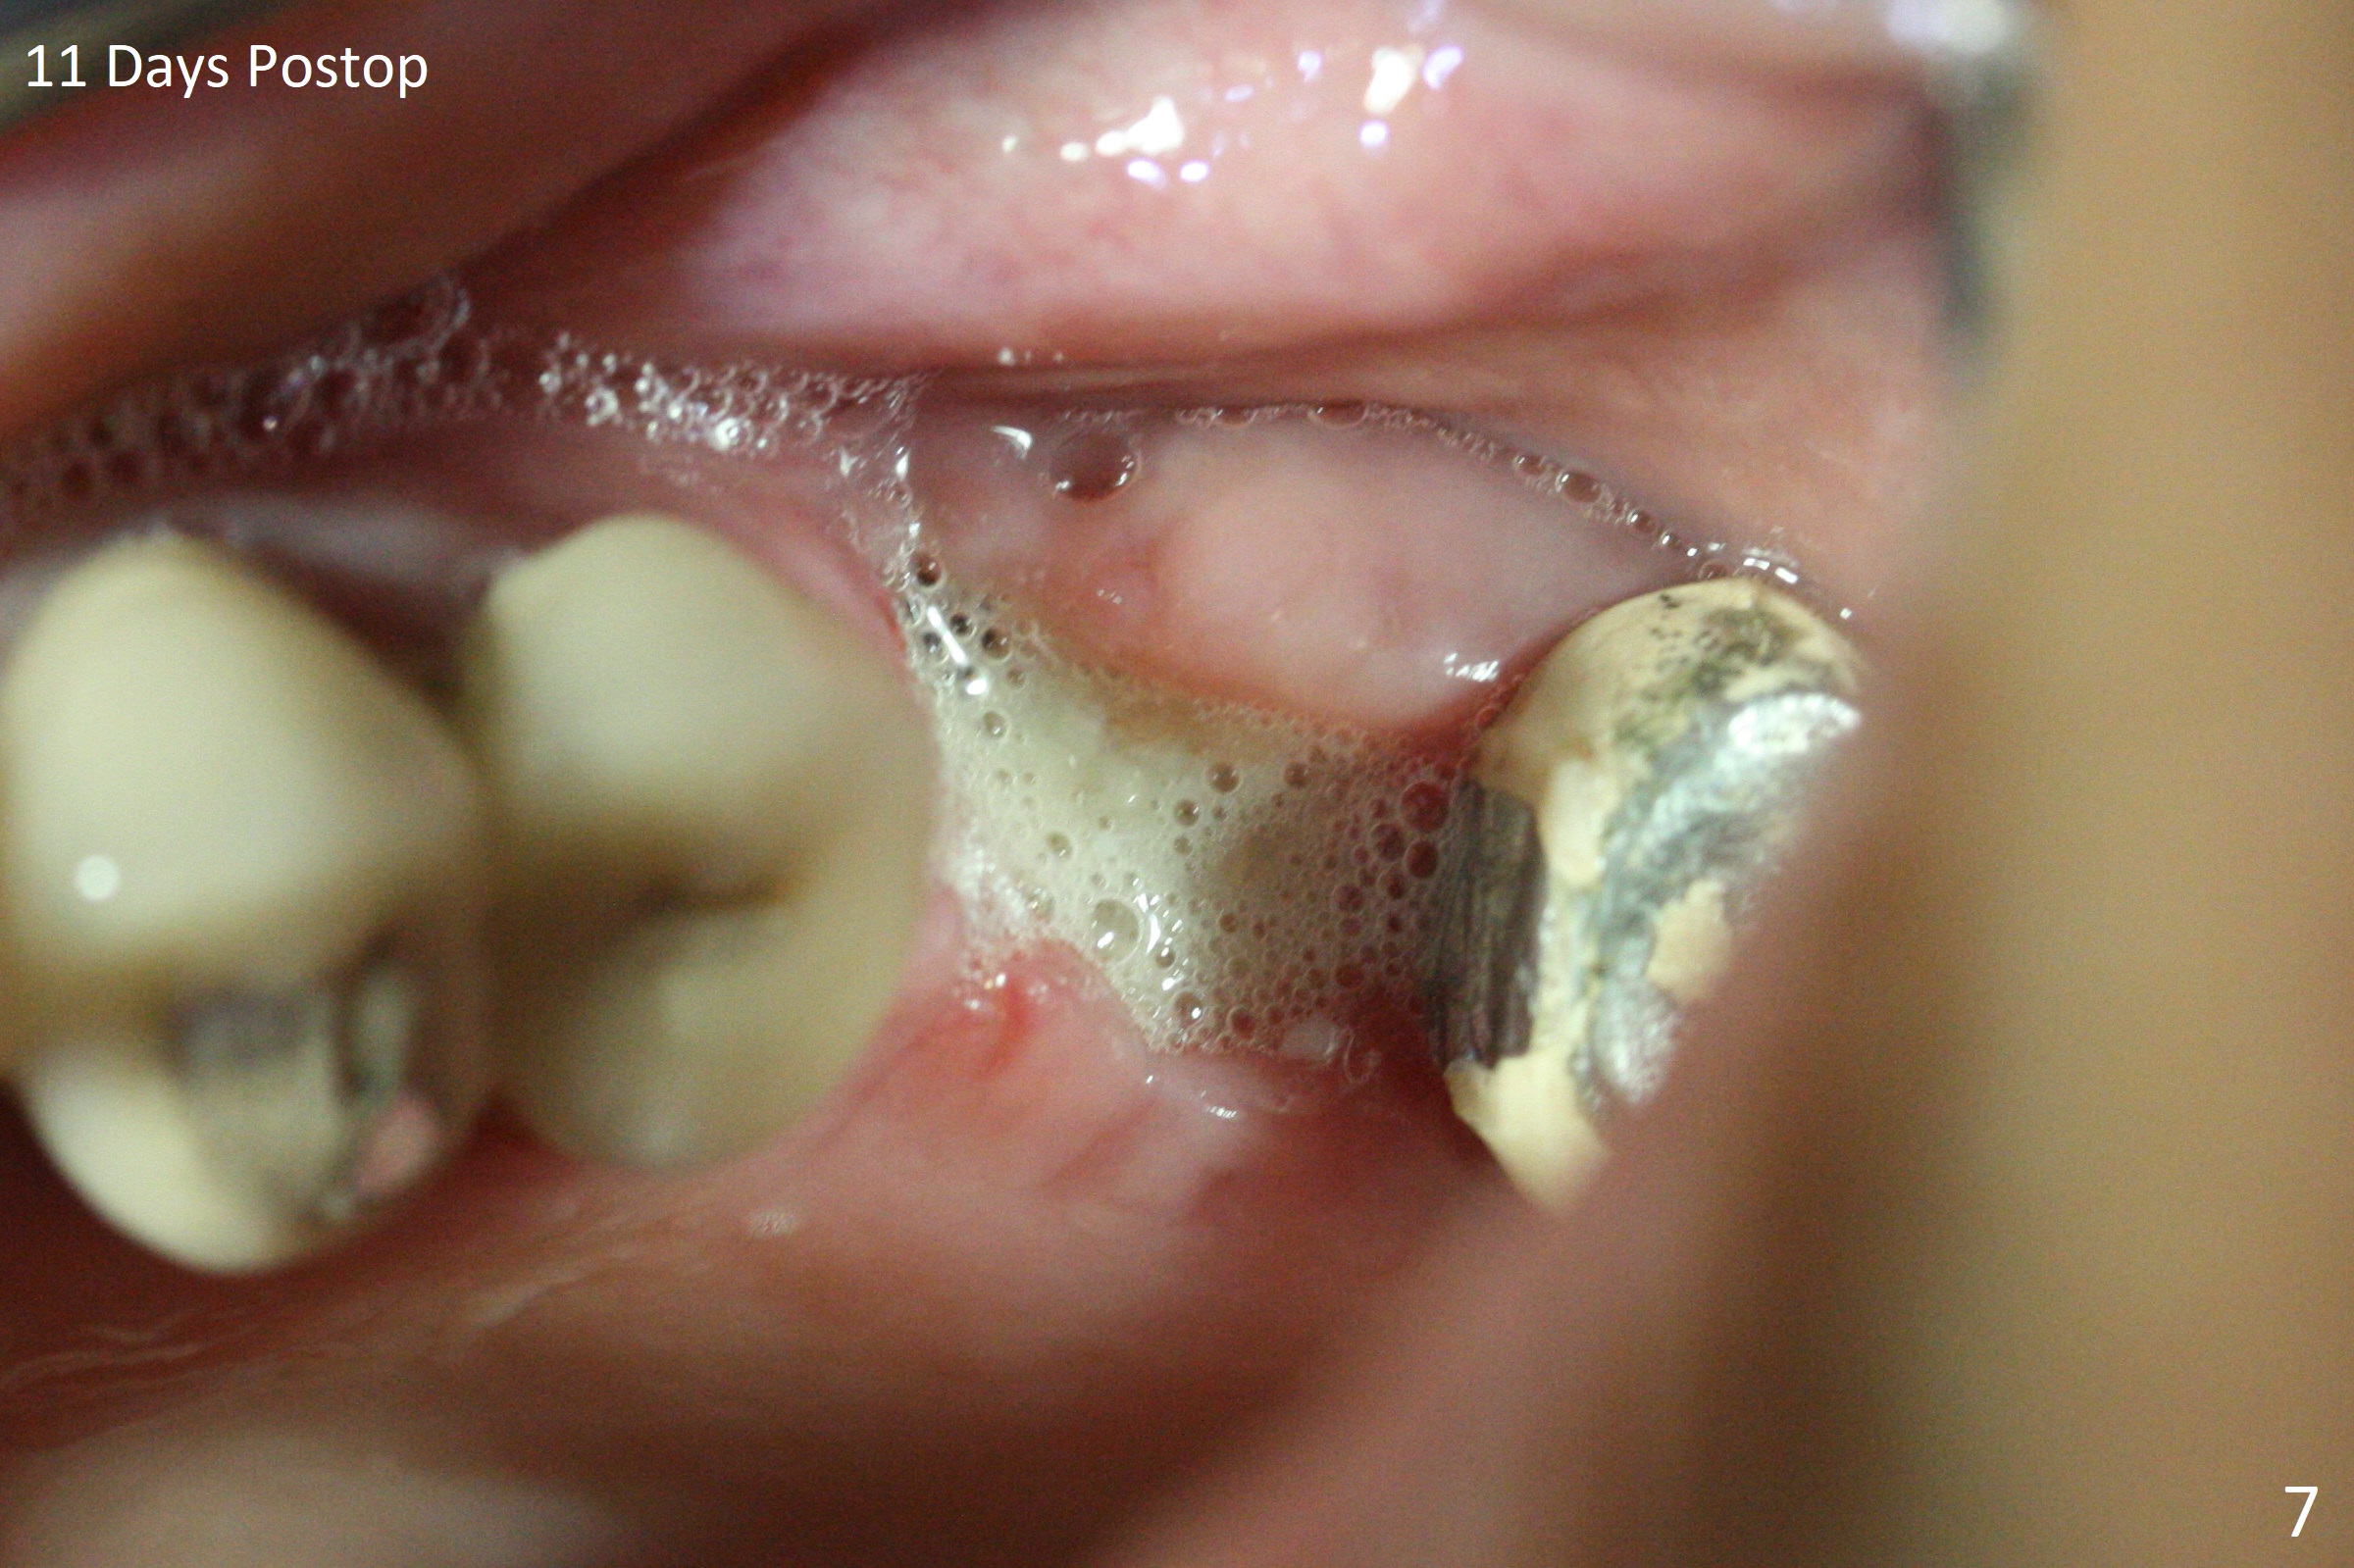

A 49-year-old woman returns for removal of the tooth #14 with loss of the buccal plate (Fig.1 red dashed line). After extraction, the buccal gingiva collapses as a dimple (Fig.2 ^). Cytoplast, a Titanium-Reinforced Non-resorbable Membrane (Fig.3), is used after bending (Fig.4) to assist in repair of the buccal plate with bone graft (Fig.5,6). As compared to Fig.1, the bone height also increases. Periodontal dressing and Cytoplast dislodge with odor 10 days postop (Fig.7,8). Periodontal dressing is re-applied. Spacer or acrylic dressing should have been used for security. In spite of the narrow ridge 5 months postop (Fig.9), a 5x11.5 mm bone level or 5x17 mm tissue-level implant is possible (Fig.10). But the implant should be placed more palatal, away from the buccal defect!